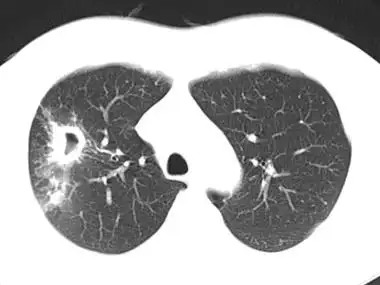

肺结核如何诊断从胸部ct到实验室检查一文讲清世界防治结核病日